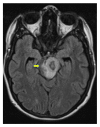

We report a case of a Somali refugee who presented in the second trimester of her first pregnancy with a four-week history of gradual right-sided sensomotoric hemisyndrome including facial palsy and left-sided paresis of the oculomotorius nerve causing drooping of the left eyelid and double vision. Cranial magnetic resonance imaging revealed a solitary brainstem lesion. Upon detection of hilar lymphadenopathy on chest X-ray (CXR), the diagnosis of disseminated tuberculosis with involvement of the central nervous system was confirmed by PCR and treatment induced with rifampicin, isoniazid, pyrazinamide, and ethambutol. The patient had a steady neurological improvement and a favorable pregnancy outcome.